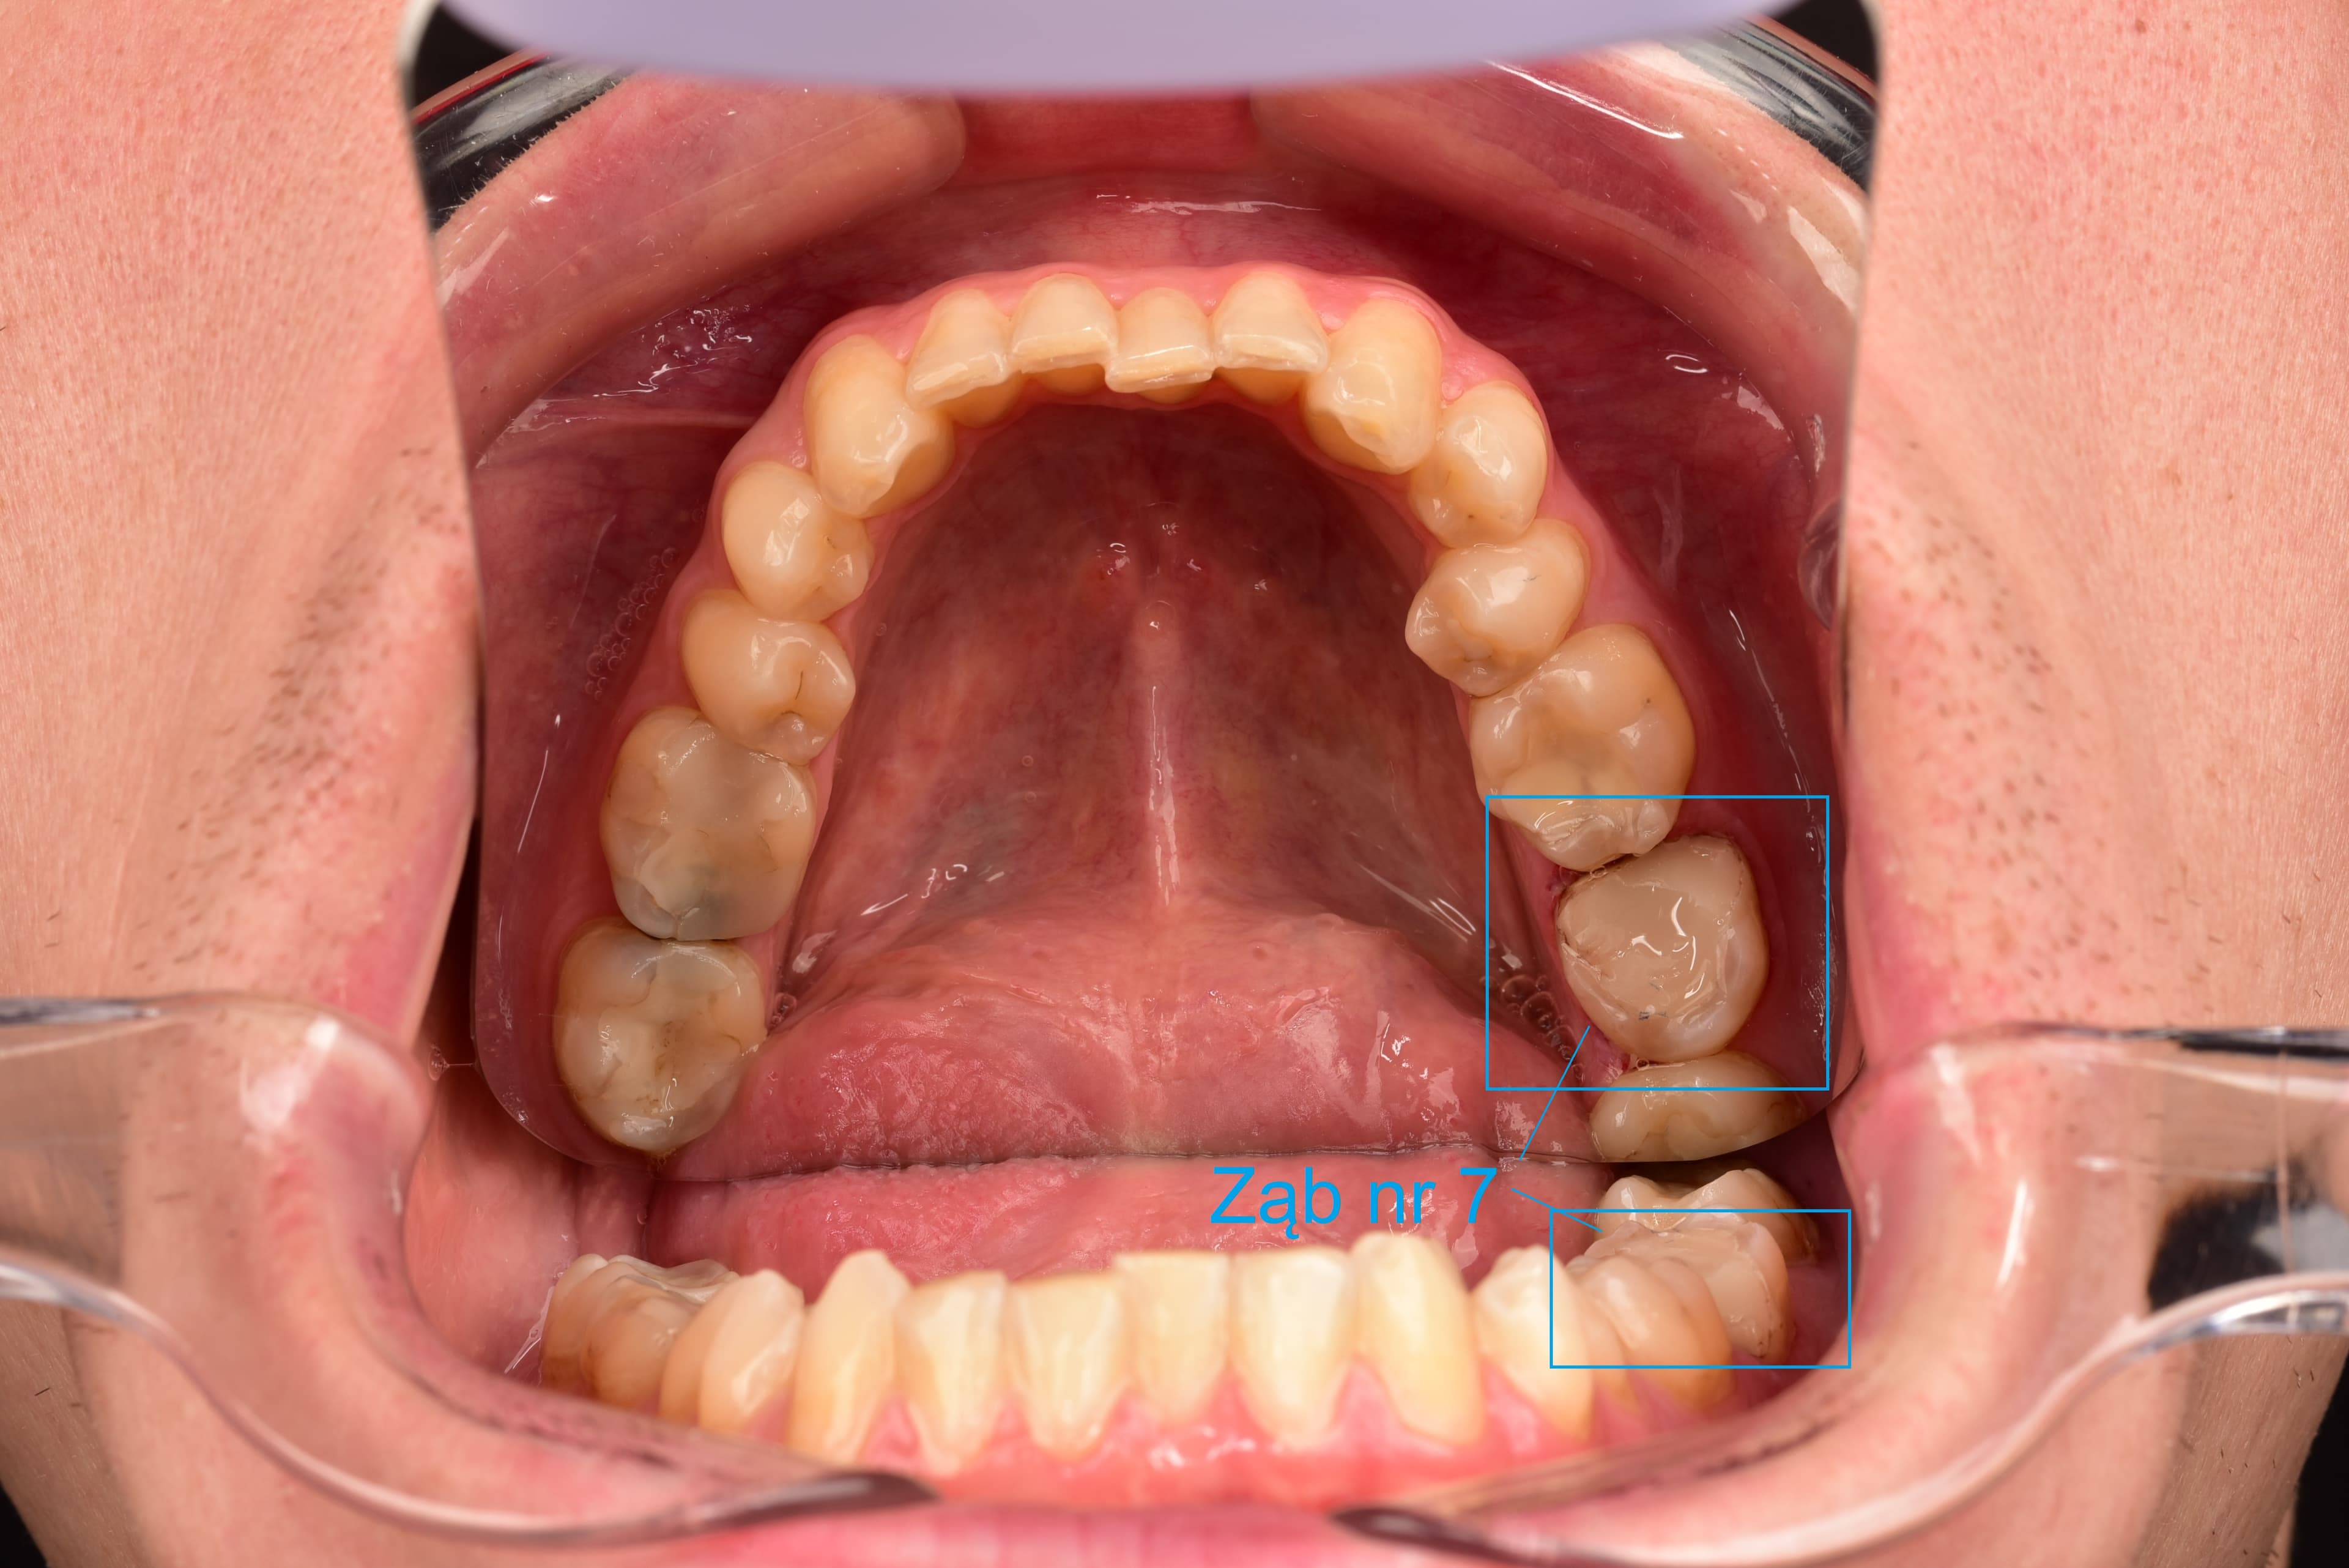

- I took a panoramic X‑ray and a bit later a CT scan of my oral cavity, so the observed progress after an appropriate time will be very accurately measurable